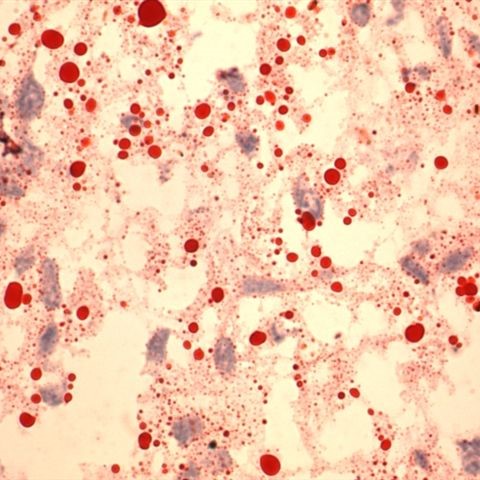

Oil red O - Kit

Four-reagent for staining lipids on cryostat tissue sections. Fixation: we recommend using saline formalin or Baker?s fixative to prevent phospholipid dissolution.